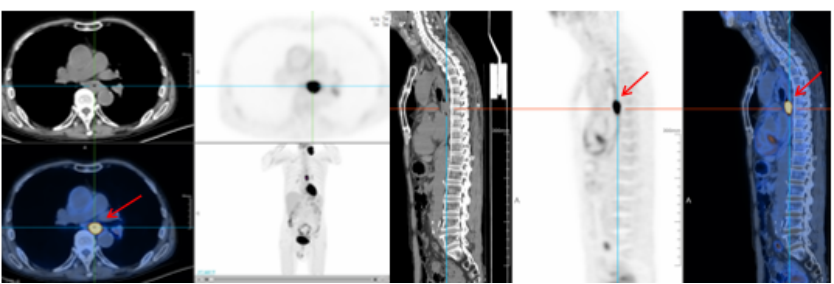

图4 男,62岁,发现左侧颈部肿物3月,无不适,穿刺活检病理:转移性鳞癌

为查找原发灶,行PET-CT检查示 食管中段癌